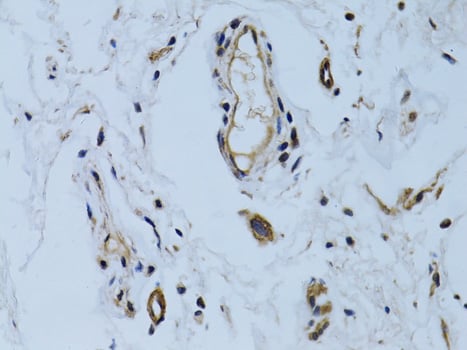

IHC (Immunohistochemistry)

(Immunohistochemistry of paraffin-embedded human breast using MCAM antibody at dilution of 1:100 (40x lens).)